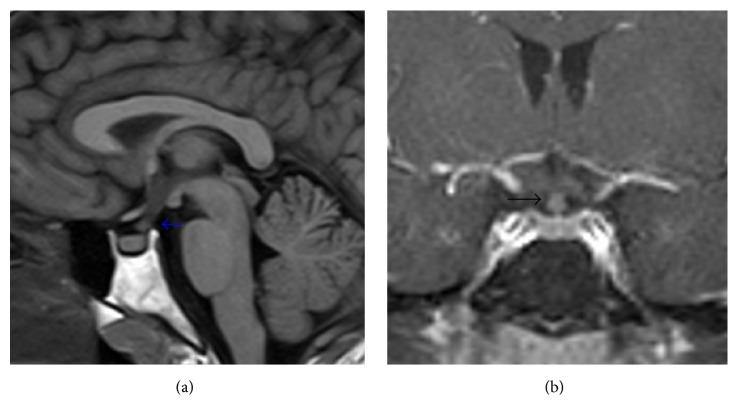

Langerhans cell histiocytosis is characterized by the abnormal nodular proliferation of histiocytes in various organ systems. Pulmonary involvement seen in young adults is nearly always seen in the context of past or current cigarette smoking. Although it tends to be a single-system disease, extrapulmonary manifestations involving the skin, bone, and hypothalamic-pituitary-axis are possible. High resolution CT (HRCT) of the thorax findings includes centrilobular nodules and cysts that are bizarre in shape, variable in size, and thin-walled. Often the diagnosis can be made based on the appropriate clinical presentation and typical imaging findings. Treatment includes smoking cessation and the potential use of glucocorticoids or cytotoxic agents depending on the severity of disease and multisystem involvement.

朗格汉斯细胞组织细胞增多症的特征是组织细胞在各个器官系统中出现异常的结节状增殖。在年轻成年人中出现的肺部受累几乎总是在过去或当前吸烟的背景下出现。尽管它往往是一种单系统疾病,但累及皮肤、骨骼和下丘脑 - 垂体轴的肺外表现也是可能的。胸部高分辨率CT(HRCT)表现包括小叶中心结节和囊肿,其形状怪异、大小不一且壁薄。通常根据适当的临床表现和典型的影像学表现即可做出诊断。治疗包括戒烟,以及根据疾病严重程度和多系统受累情况可能使用糖皮质激素或细胞毒性药物。